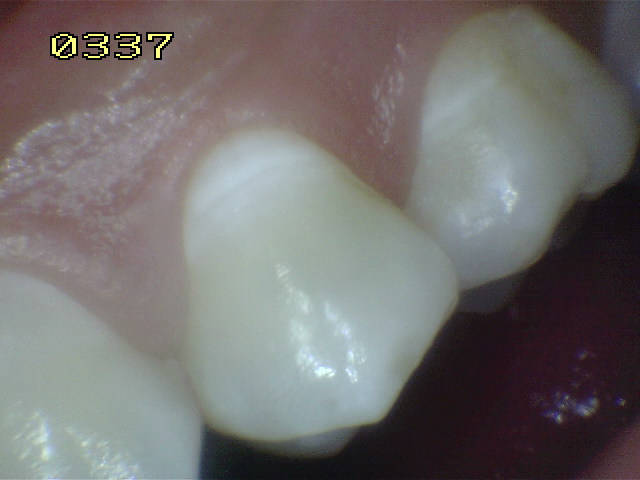

Esmalte liso, traslucido y

cristalino, con finas bandas horizontales de color

blanquecino. |